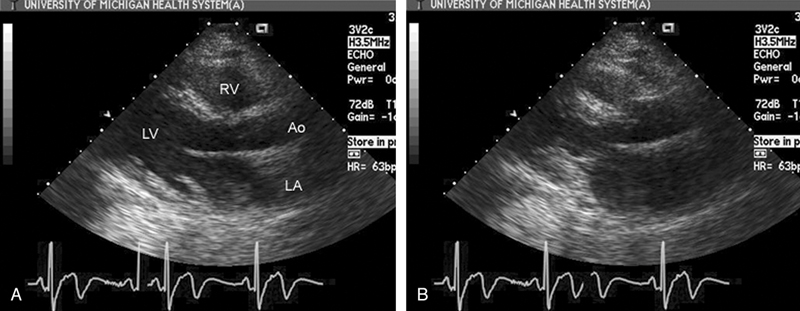

فحوصات تشخيصية لبعض امراض القلب والشرايين التاجية